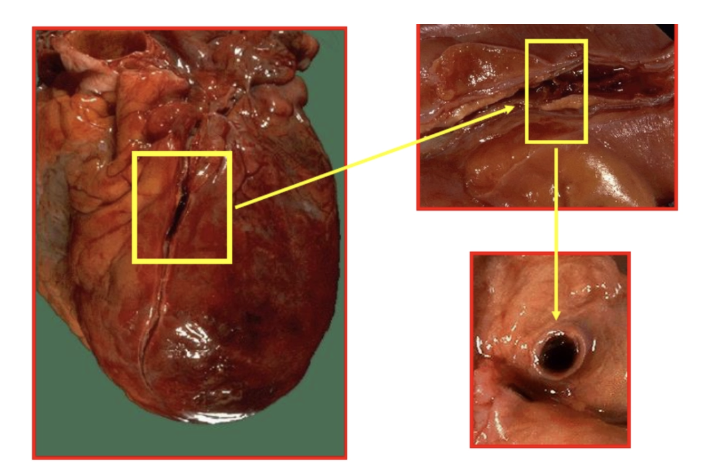

Hemopericardio: acumulación de sangre, principalmente por rotura cardiaca